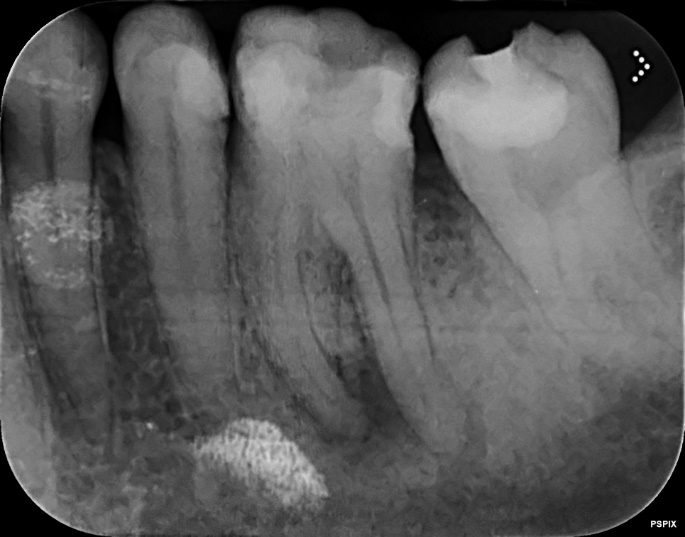

Lower Molar and premolar Primary root canal treatment